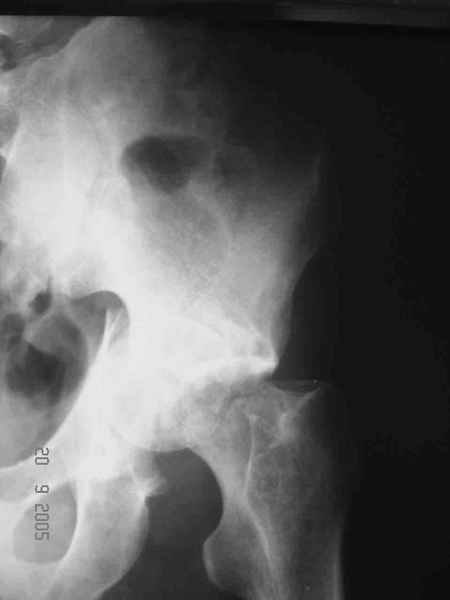

Привет! Вот недавно прооперировали похожий на ваш случай - впадина + шейка (правда у нас впадина поперечный+задний край). После травмы прошло 4 недели. мужчине 46 лет. С такой комбинацией все показания к первичному протезированию. Морально и технически мы к этому уже созрели.Но больной не собрал денег на протез. Выполнили остеосинтез впадины и шейки, прекрасно понимая, что головка вскоре рассосется, мы хотя бы надемся что к этому времени таз срастется, как говорится создали все условия для дальнейшего протезирования (может, и протез в последующем подешевле будет, в смысле, без укрепляющего кольца?). Привет Рункову!

Привет Алекей! Сделано неплохо, поздравляю, хотя второй винтик можно было бы и подлиннее в шейку загнать! Пара вопроов: доступ такой же? головка была свободной или висела на капсуле?

Согласен, можно было и подлиннее. Доступ такой же - чрезвертельный, только разрез кожи прямой (а не Y, чего то я разницы не ощущаю). Головка была абсолютно свободной (то есть во время остеосинтеза таза лежала в стакане и не мешалась). Шансов, что она прирастет 0,00001%. Хотели даже выбросить, но привинтили как временный биологический протез (читай свободный трансплантат), чтоб на период срастания таза бедро проксимально не ушло (может ортопеды потом спасибо скажут). Ну а у вас первичное протезирование при переломе впадины тоже пока полько в планах?